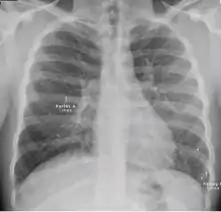

Chest x-ray of pleural thickening post-primary tuberculosis

1. Pleural thickening - Irregularity or abnormal prominence of the pleural margin, including apical capping (thickening of the pleura in the apical region). Pleural thickening can be calcified.

2. Diaphragmatic tenting - A localized accentuation of the normal convexity of the hemidiaphragm as if "pulled upwards by a string."

3. Blunting of costophrenic angle (in adults)—Loss of sharpness of one or both costophrenic angles. Blunting can be related to a small amount of fluid in the pleural space or to pleural thickening and, by itself, is a non-specific finding (except in children, when even minor blunting may suggest active TB). In contrast a large pleural effusion, or the presence of a significant amount of fluid in the pleural space, may be a sign of active TB at any age.